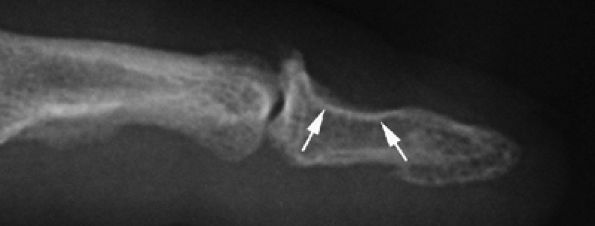

FIGURE 11.115 ● Mucoid pseudocyst. Lateral view radiograph showing distal interphalangeal joint osteoarthritis with bone pressure erosion (arrows) of the dorsal aspect of the distal phalanx.

|

![]() |

FIGURE 11.116 ● Mucoid pseudocyst. (A) PA view photograph showing thickening of the posterior nail fold (asterisk) and nail groove (arrows) on the midline due to matrix compression. (B) Sagittal STIR image displaying a bilobed cyst of the posterior nail fold (arrows) close to the insertion of the extensor tendon (asterisk). Note the intralesional septum (black arrowheads). The cyst causes deep displacement of the nail root (white arrowhead).